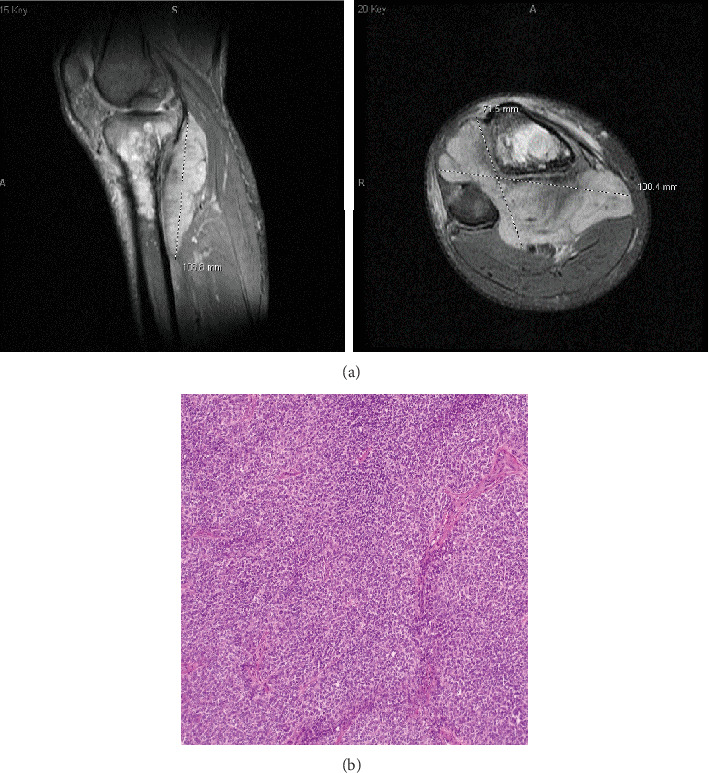

骨与软组织肉瘤包括 70 多种组织学亚型,由于其特征相互重叠,给诊断带来了挑战。荧光原位杂交(FISH)和反转录聚合酶链反应(RT-PCR)等分子分析有助于确定特定的基因组改变,但往往有局限性,尤其是在之前的组织学检查结果不确定的情况下。下一代测序(NGS)通过有针对性的测序面板提供高通量检测,解决了这些局限性。本病例系列着重介绍了 NGS 在诊断两名免疫生物学不明确的尤文肉瘤(ES)和透明细胞肉瘤(CCS)儿科患者中的作用,强调了 NGS 作为实体瘤诊断利器的作用。

Bone and soft-tissue sarcomas encompass over 70 histologic subtypes, posing diagnostic challenges due to overlapping characteristics. Molecular analyses, such as fluorescence in situ hybridization (FISH) and reverse transcription polymerase chain reaction (RT-PCR), aid in identifying specific genomic alterations but are often limited, particularly when prior histological findings are inconclusive. Next-generation sequencing (NGS) offers high-throughput testing via a targeted sequencing panel, addressing these limitations. This case series highlights the utility of NGS in diagnosing two pediatric patients with immunobiologically ambiguous Ewing sarcoma (ES) and clear cell sarcoma (CCS), emphasizing its role as a powerful tool in solid tumor diagnosis.